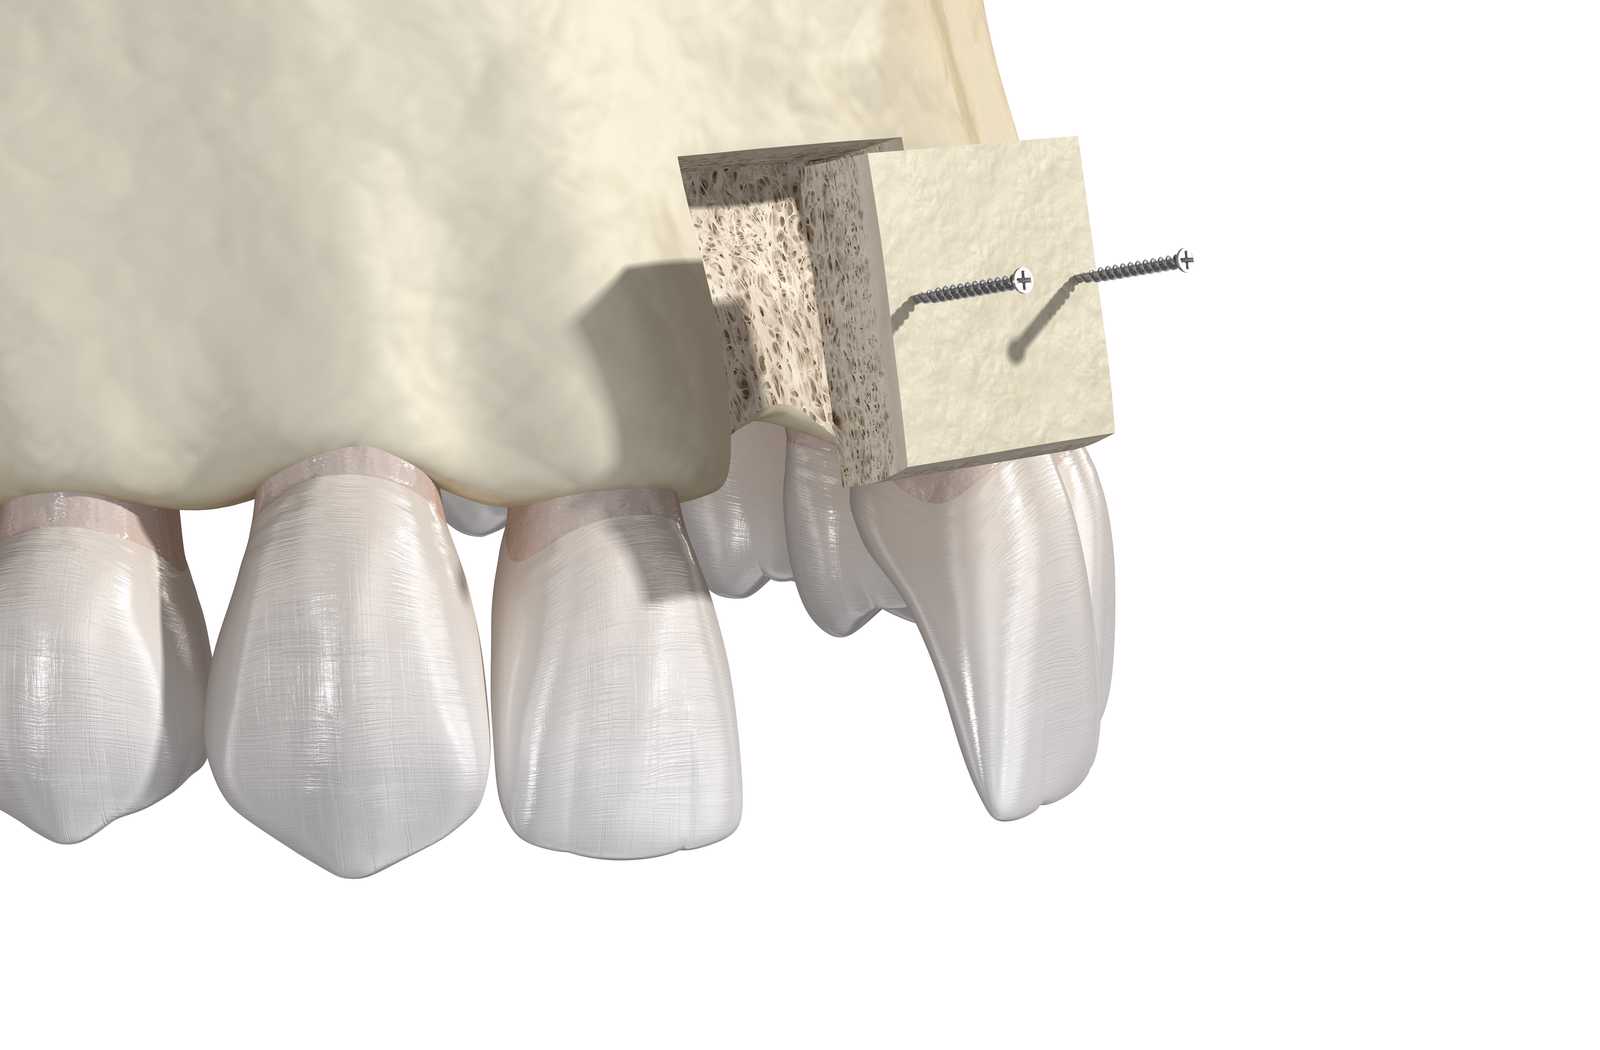

Una de las técnicas más avanzadas para la regeneración ósea es la técnica de Khoury, que utiliza finas láminas de hueso autólogo tomadas del propio paciente (normalmente de la rama mandibular o el mentón). Estas láminas se fijan en la zona receptora para crear una estructura tridimensional que se rellena con hueso particulado, también autólogo. Esta «caja ósea» favorece una regeneración estable y natural.

El uso exclusivo de hueso del propio paciente hace que la integración sea óptima, con mínima posibilidad de rechazo o complicaciones, lo que convierte a la técnica de Khoury en una de las opciones más seguras y eficaces en casos de atrofias óseas severas.